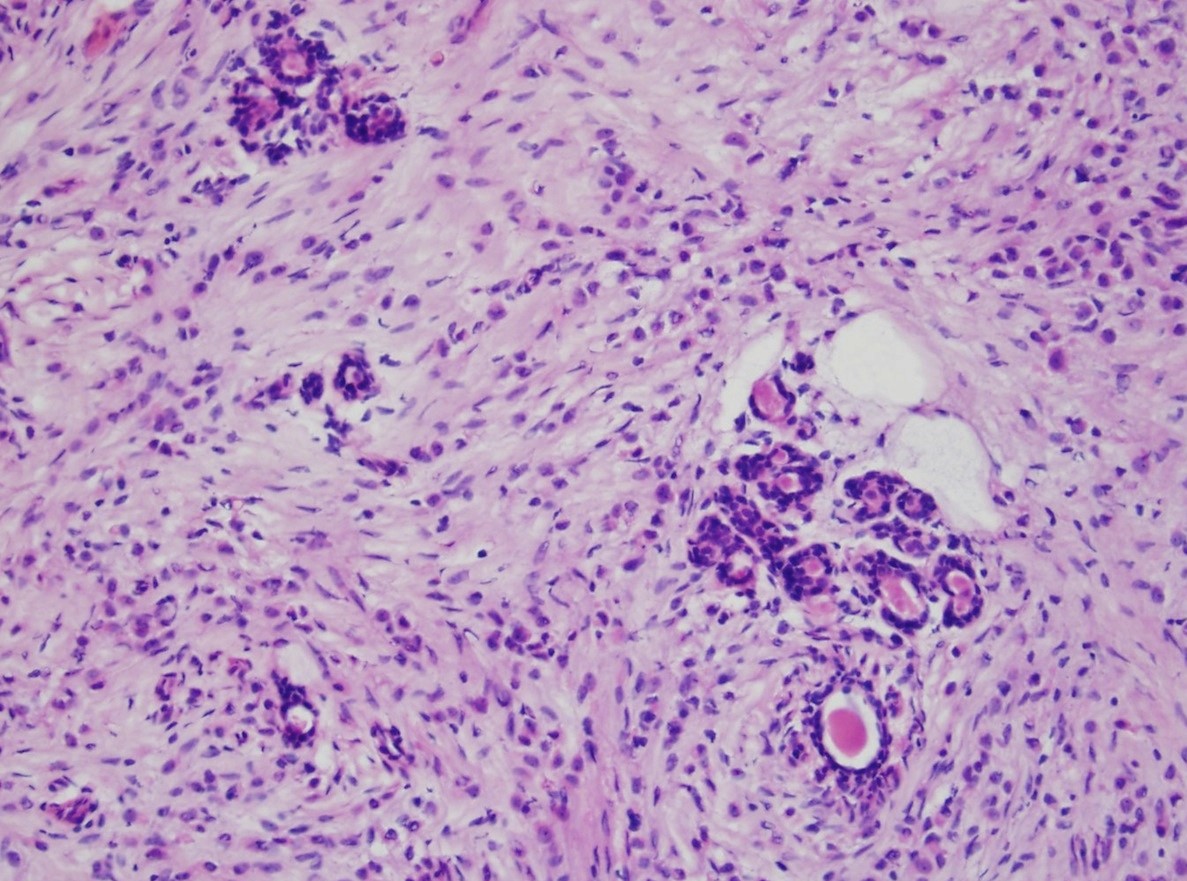

Microscopic (histologic) description

- Tumor cells arranged in single files, cords and single cells (Breast Cancer Res 2015;17:12)

- Can be arranged concentrically around normal ducts, giving a targetoid appearance

- Tumor cells discohesive, small, monomorphic and lacking marked atypia

- Round or notched ovoid nuclei, usually grade 1 or 2 nuclear score

- Scant cytoplasm, occasional with intracytoplasmic lumen

- Mitosis infrequent

- Desmoplastic reaction and necrosis uncommon

- Requires high index of suspicion for metastasis

- Single and scattered tumor cells with mild atypia requires examination on high power magnification with caution (Int J Surg Case Rep 2021;80:105612)

Microscopic (histologic) images